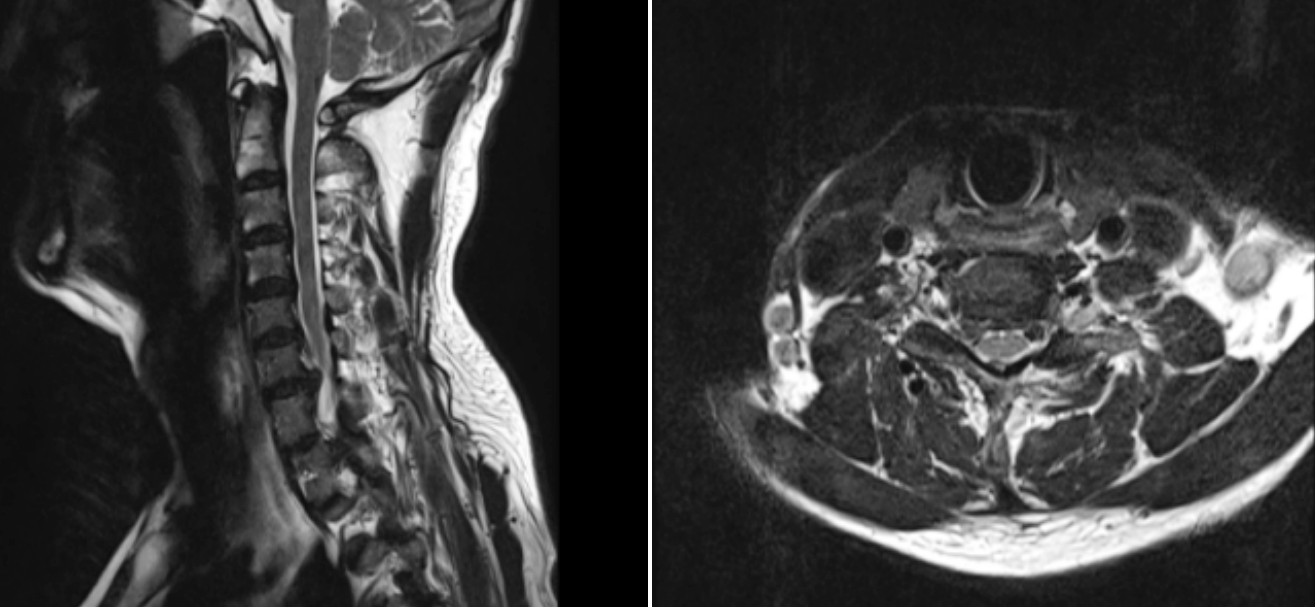

術(shù)前MRI圖像

患者,男,65歲,近期飽受右側(cè)上肢疼痛與麻木之苦,歷時三周之久。在外院嘗試保守治療措施,效果不佳,來我院就診。經(jīng)過醫(yī)療團隊周密而細致的檢查,患者被明確診斷為“神經(jīng)根型頸椎病”,精準地指出了其癥狀的根本原因。